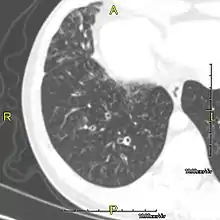

The main consequence of impaired ciliary function is reduced or absent mucus clearance from the lungs, and susceptibility to chronic recurrent respiratory infections, including sinusitis, bronchitis, pneumonia, and otitis media. Progressive damage to the respiratory system is common, including progressive bronchiectasis beginning in early childhood, and sinus disease (sometimes becoming severe in adults). However, diagnosis is often missed early in life despite the characteristic signs and symptoms.[1] In males, immotility of sperm can lead to infertility, although conception remains possible through the use of in vitro fertilization, there also are reported cases where sperm were able to move.[2] Trials have also shown that there is a marked reduction in fertility in female sufferers of Kartagener's syndrome due to dysfunction of the oviductal cilia.[3]

Many affected individuals experience hearing loss and show symptoms of otitis media which demonstrates variable responsiveness to the insertion of myringotomy tubes or grommets. Some patients have a poor sense of smell, which is believed to accompany high mucus production in the sinuses (although others report normal – or even acute – sensitivity to smell and taste). Clinical progression of the disease is variable, with lung transplantation required in severe cases. Susceptibility to infections can be drastically reduced by an early diagnosis. Treatment with various chest physiotherapy techniques has been observed to reduce the incidence of lung infection and to slow the progression of bronchiectasis dramatically. Aggressive treatment of sinus disease beginning at an early age is believed to slow long-term sinus damage (although this has not yet been adequately documented). Aggressive measures to enhance clearance of mucus, prevent respiratory infections, and treat bacterial superinfections have been observed to slow lung-disease progression. Although the true incidence of the disease is unknown, it is estimated to be 1 in 32,000,[4] although the actual incidence may be as high as 1 in 15,000.

When accompanied by the combination of situs inversus (reversal of the internal organs), chronic sinusitis, and bronchiectasis, it is known as Kartagener syndrome (only 50% of primary ciliary dyskinesia cases include situs inversus).